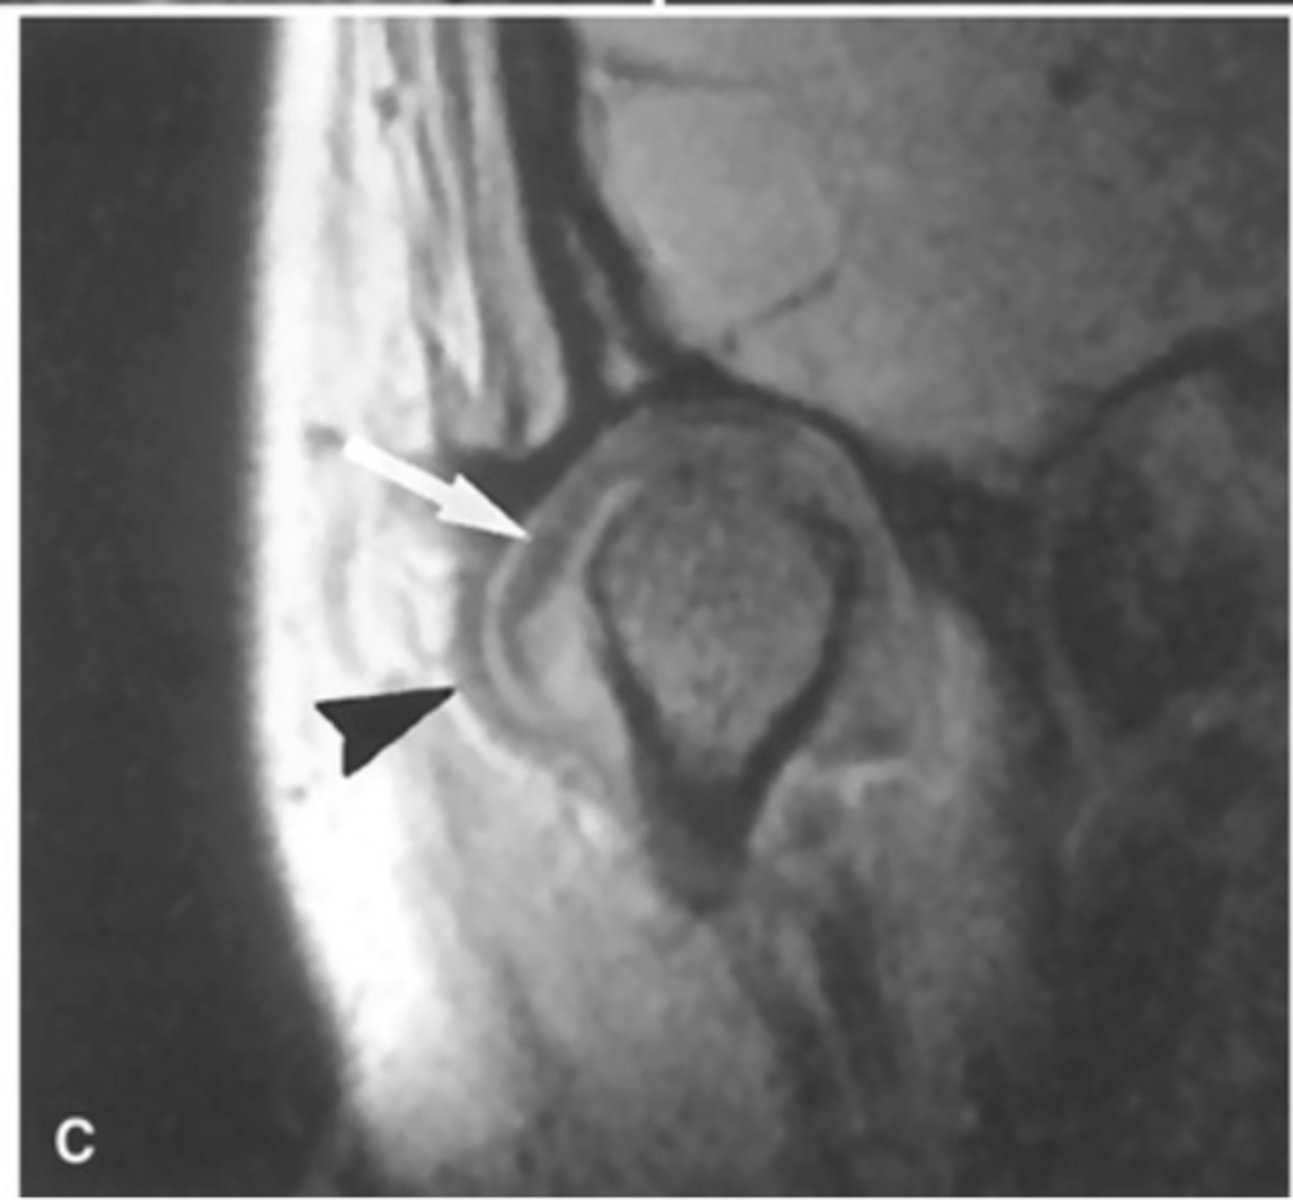

MRI image of the TMJ allowing for visualization of the condylar disc.

What is the image showing?

anteriorly displaced (the posterior band is anterior to the condyle)

The MRI is showing the disc ________ ______

laterally displaced (the joint capsule is bulging out laterally)